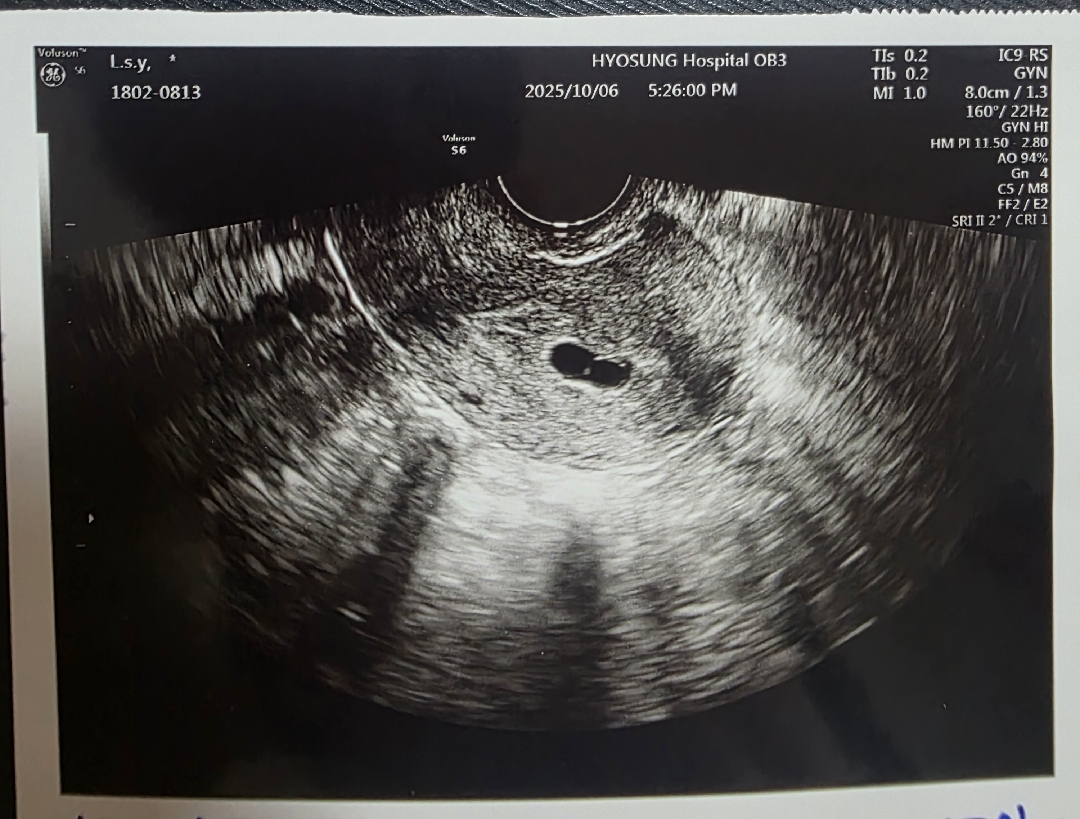

7주6일차인 산모입니다 10월1일에 초음파상 애기가 심각할정도로 안크고있다는 말을듣고 피검사하고 2일도 피검사해서 수치비교해보고 중절결정하자하셨는대 수치는 괜찮다는 소리듣고 조금안심할찰나 4일부터6일오늘까지 갈색혈이 묻어나오고 6일새벽에 없던 복통도있고해서방금 응급진료받고왔습니다 애기집모양도안좋고 애기심장도안보인다고 10일 진료일까지 지켜보자하네요 저같은 산모님들 계실까요? ㅠㅠ 작년 3월에 자궁외임신겪고 찾아온 소중한아긴대 눈물밖에안나오네요 이상황이